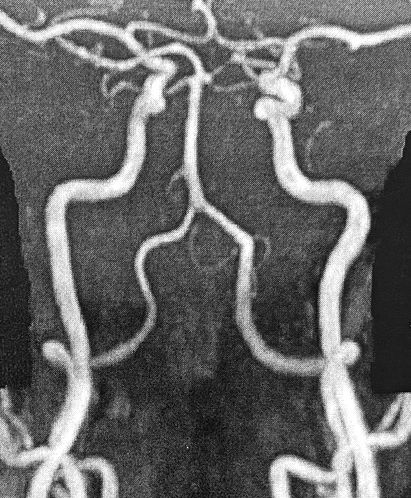

椎骨動脈は首の左右に一本ずつあります。逆Yの字状になっていますが、形や血流には個人差が大きく、画像のように綺麗な形とは限りません。

椎骨動脈の拡大撮影画像